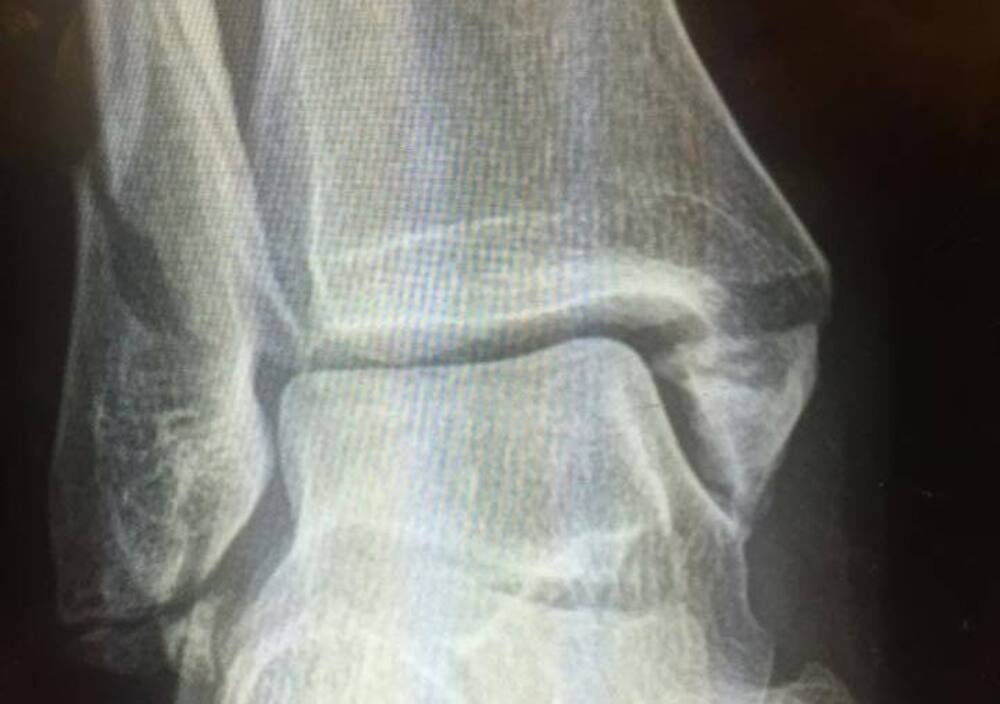

Ricoverato in ospedale è stato sottoposto ad una operazione che lo costringerà ad almeno due settimane di riposo. Troy rimane comunque fiducioso e su Facebook scrive di voler tornare in sella per il round dell'11 luglio a Indy Mile. La foto post operazione della caviglia, pubblicata sul social network, non rassicura molto i suoi fan, ma sappiamo che l'australiano farà di tutto pur di ripresentarsi al più presto sugli ovali di Flat Track.